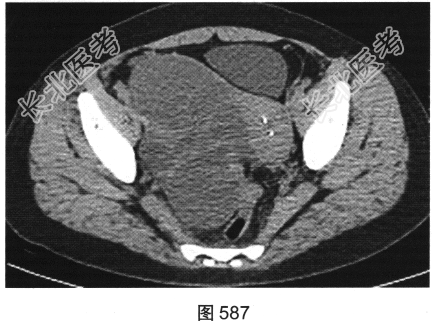

患者女性,38岁,因“间断性下腹部疼痛1周”入院。既往:否认肝炎、结核病史。查体:下腹部压痛。患者行腹部CT检查,见图582~图589。

- 多项选择题1.结合病史及影像学检查结果,可以考虑患者为以下哪些疾病( )

A、肝脏囊肿+附件囊腺瘤

B、肝脏转移瘤+附件囊腺癌

C、肝脏炎性假瘤+附件囊肿

D、肝脏炎性假瘤+输卵管积液

E、肝脏转移瘤+附件囊腺瘤

F、肝脏转移瘤+附件转移瘤

- 多项选择题4.[提示]肠镜活检病理:中分化腺癌。糖链抗原724: 46.46U/ml,癌胚抗原292.61ng/ml, 糖链抗原242:58.13U/ml, 糖链抗原199:65.78U/ml。结合影像、临床、实验室检查及镜检病理结果, 该患者术前诊断应考虑为( )

A、直肠癌,伴肝脏炎性假瘤,右侧附件转移瘤

B、直肠癌,伴肝脏转移瘤及右侧附件转移瘤

C、直肠癌,伴肝脏转移瘤,右侧附件囊腺瘤

D、直肠癌,伴肝脏转移瘤,右侧附件囊腺癌

E、直肠癌,伴肝脏转移瘤.右侧附件子宫内膜异位症

F、直肠癌,伴肝脏炎性假瘤,右侧附件囊腺瘤